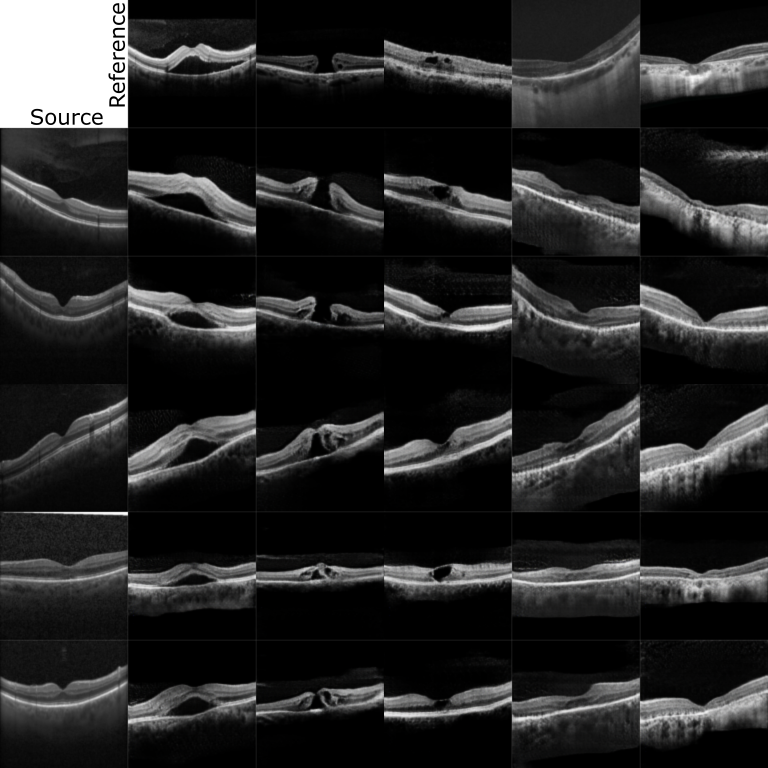

Refer to caption

Figure 4: Reference based synthesis on Taekun dataset. The first column presents the normal images that are given to our model as the source images while the first row corresponds to various pathologies that are provided as reference images. All the other images are outputs generated by our model translating from normal b-scan to pathological b-scan. Images in each row represent generated outputs for the same source image with different styles or domains. It can be noted that the source domain characteristics are well preserved while translating into the target domain.

Qualitative evaluation: Figure 2 and 3 compares the generated images by the three models for the considered two datasets. We can observe that in Figure 2 both CycleGAN and our model generate good quality images while MUNIT is still learning on Taekun dataset. The style encoder in the MUNIT needs to be trained along with the generator model which makes the training complex and slow, which is overcome by our pre-trained style encoder thus making the convergence faster. And in Figure 3 for Kermany dataset, our pre-trained style encoder shows its ability to capture representations that are not prevalent and generate pathologies, where both CycleGAN and MUNIT fail to do so. Figure 4 shows the generation of pathological images for various input and reference images. We can see that the proposed model generates the reference pathology while preserving the content characteristics of the input image.